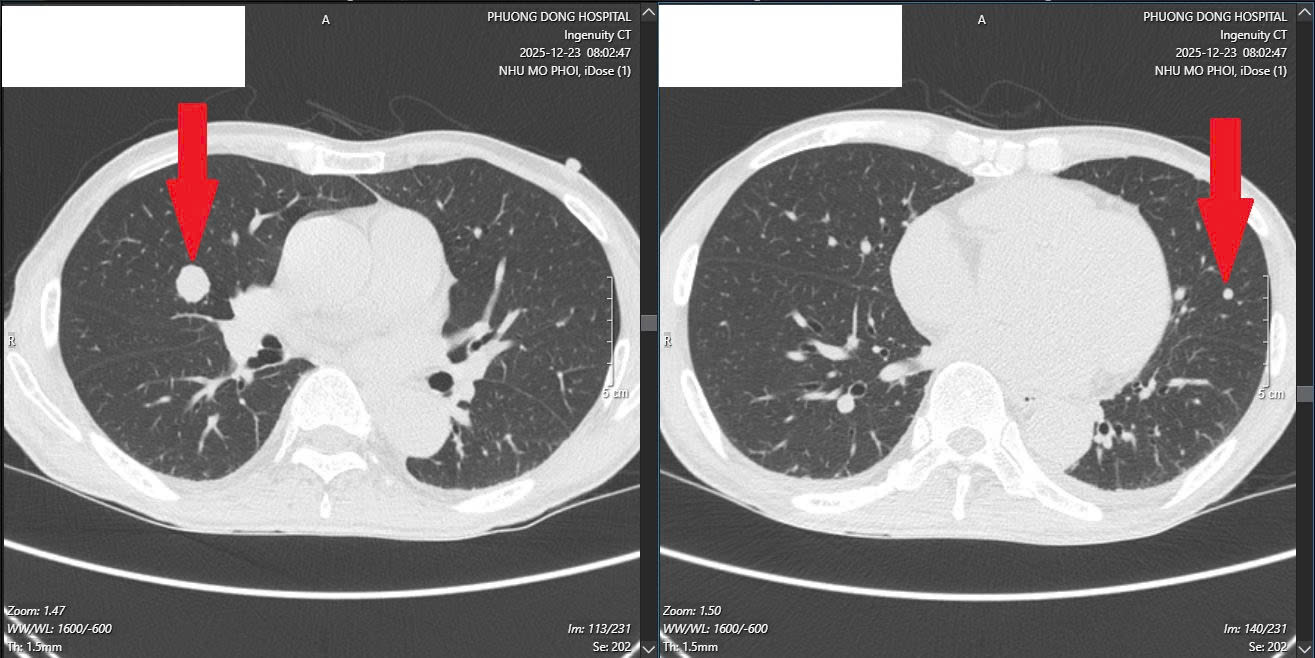

Các bác sĩ buộc phải phẫu thuật cấp cứu, làm hậu môn nhân tạo để giải phóng tình trạng tắc nghẽn phân. Đáng nói, việc từ chối điều trị ban đầu đã khiến bệnh tiến triển nặng nề hơn rất nhiều: khối u gan di căn đã to trên 10cm, xuất hiện thêm nhiều nốt di căn ở cả hai phổi.

Khối u di căn xa tới phổi (Ảnh: BSCC).